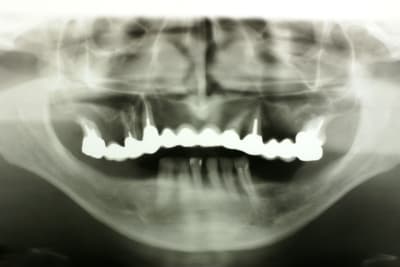

Avec un pano de m..... ;)

çà c'est clair!!!(contrairement à la pano...)

Ca tiendra certainement, mais a la pano c'est pas beau, surtout avec cette qualité.